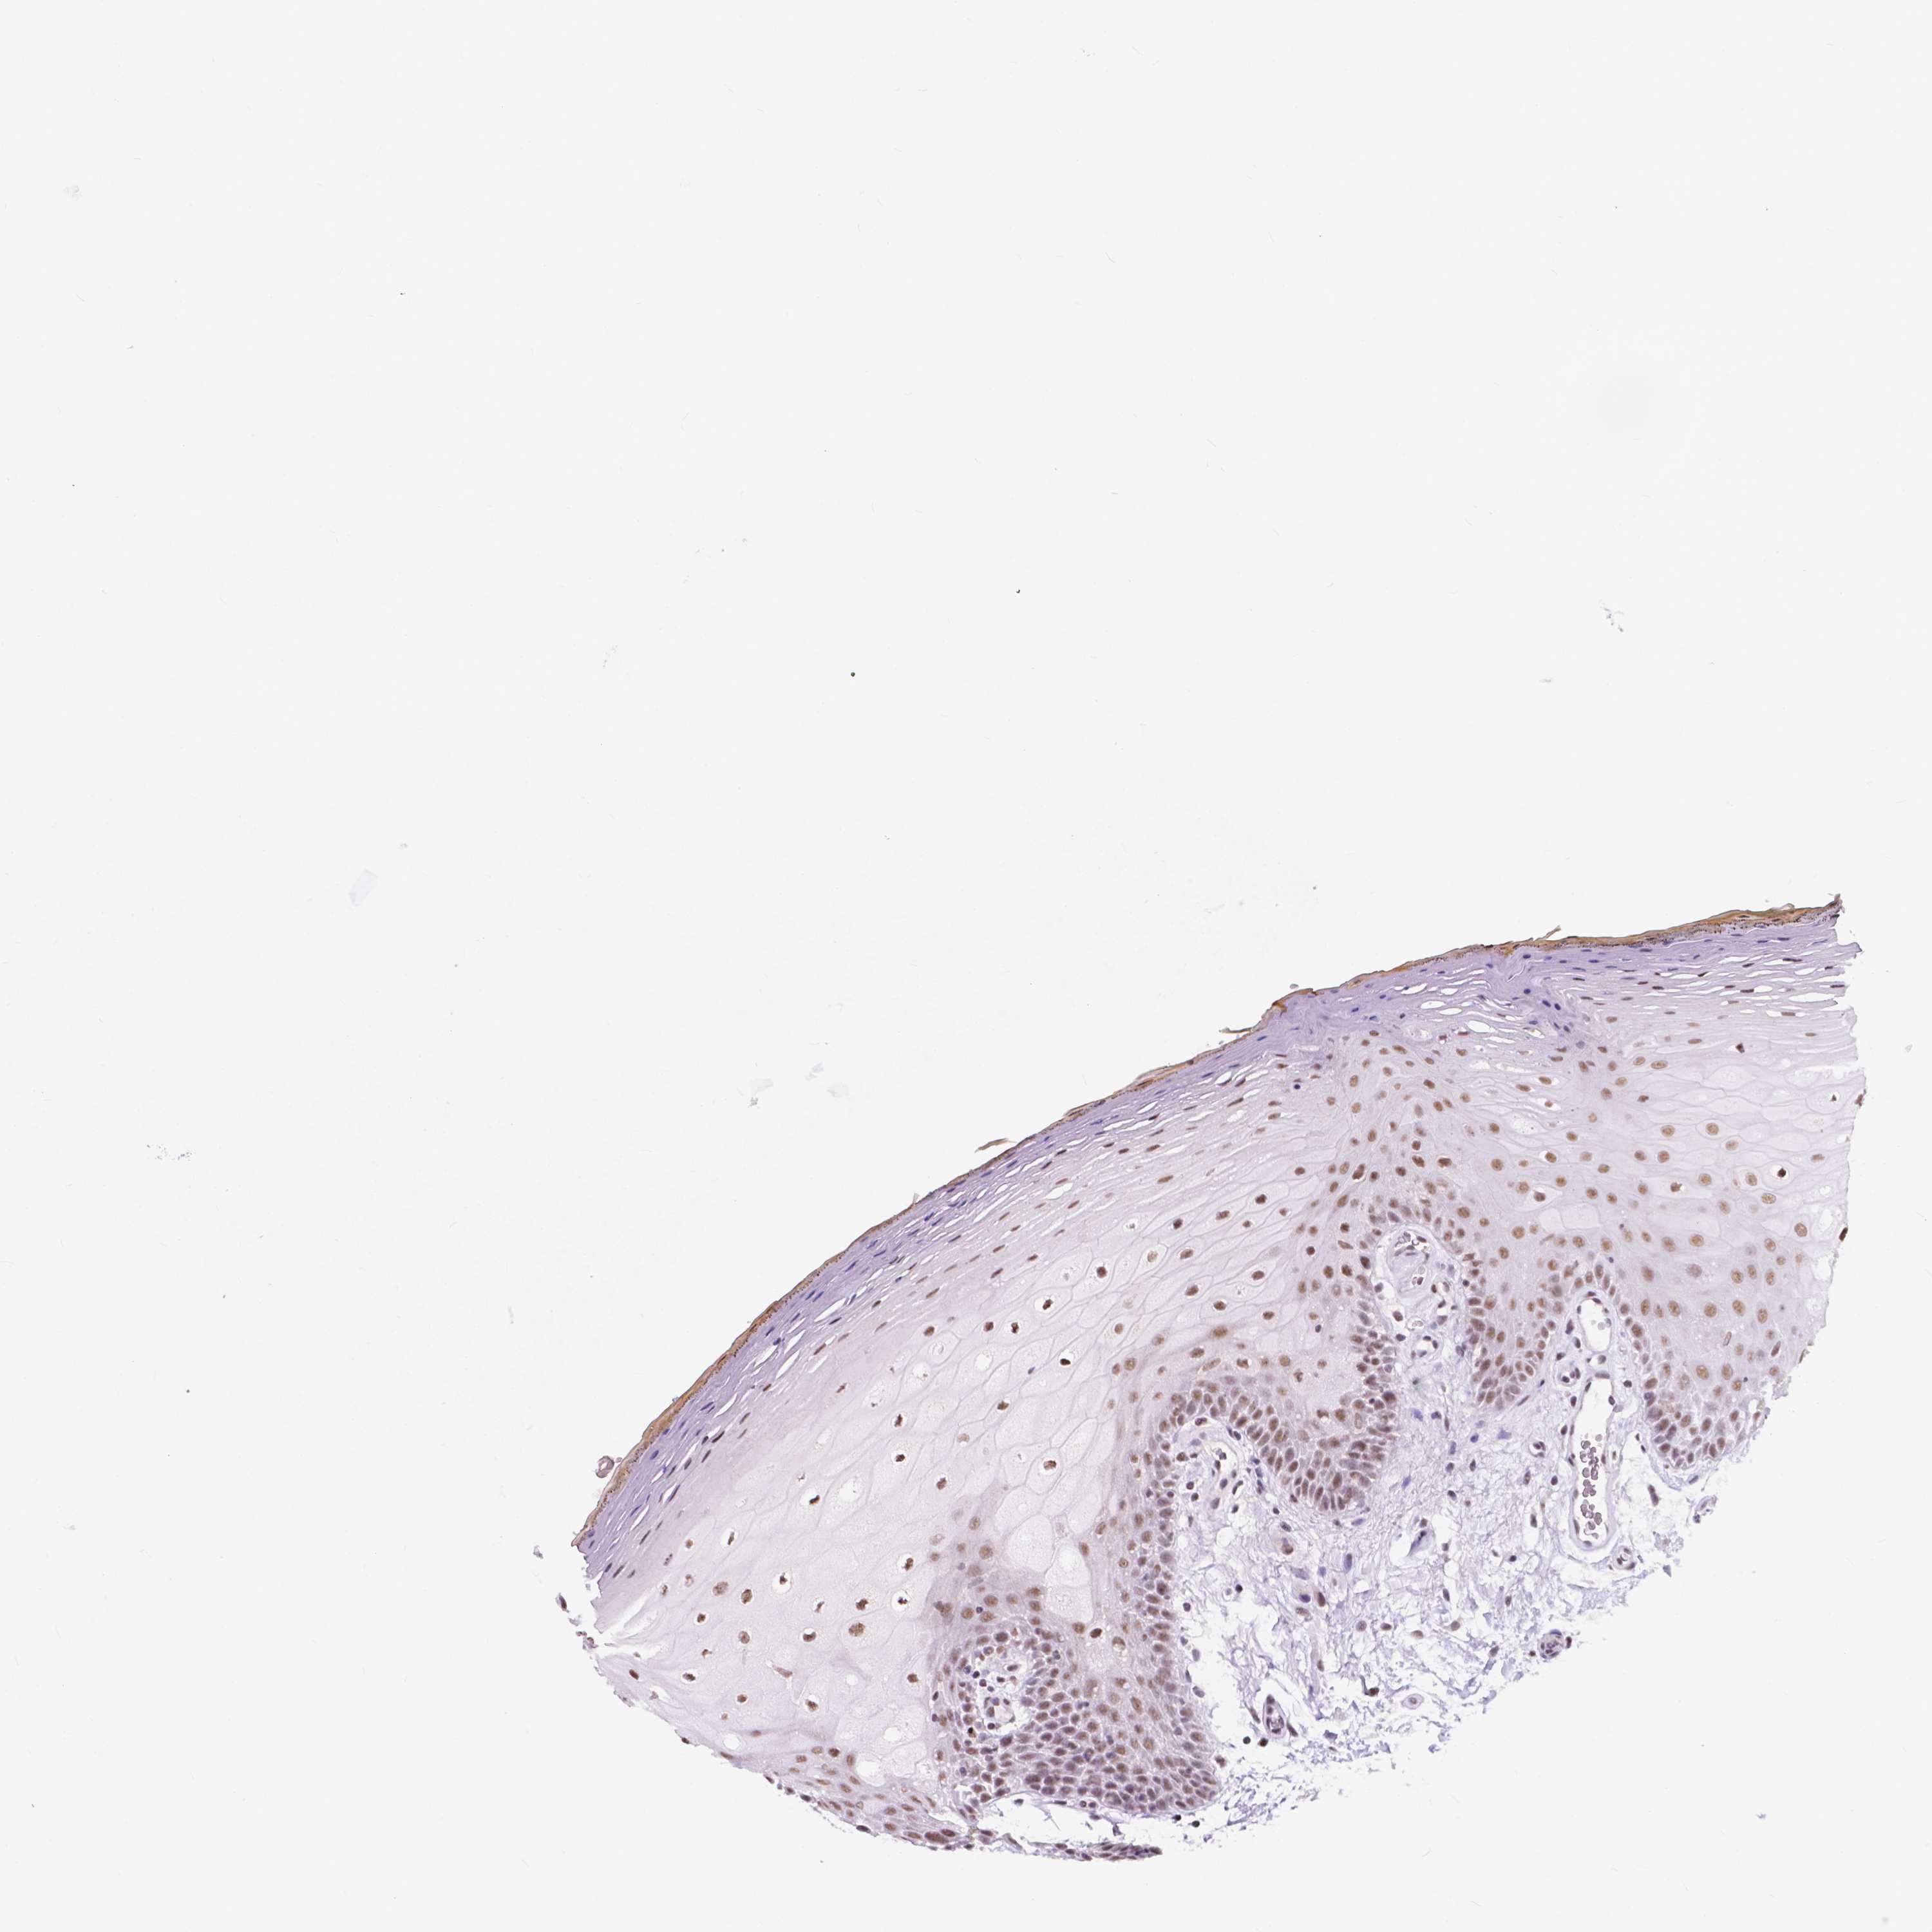

TISSUE PRIMARY DATA ORAL MUCOSA Show tissue menu

ORAL MUCOSA - Antibody stainingi

Antibody staining in the annotated cell types in the current human tissue is reported as not detected, low, medium, or high, based on conventional immunohistochemistry profiling in selected tissues. This score is based on the combination of the staining intensity and fraction of stained cells.

Each image is clickable and will lead to virtual microscopy that enables deeper exploration of all samples and also displays staining intensity scores, fraction scores and subcellular localization as well as patient and tissue information for each sample.

Antibody HPA067881

Squamous epithelial cells Medium